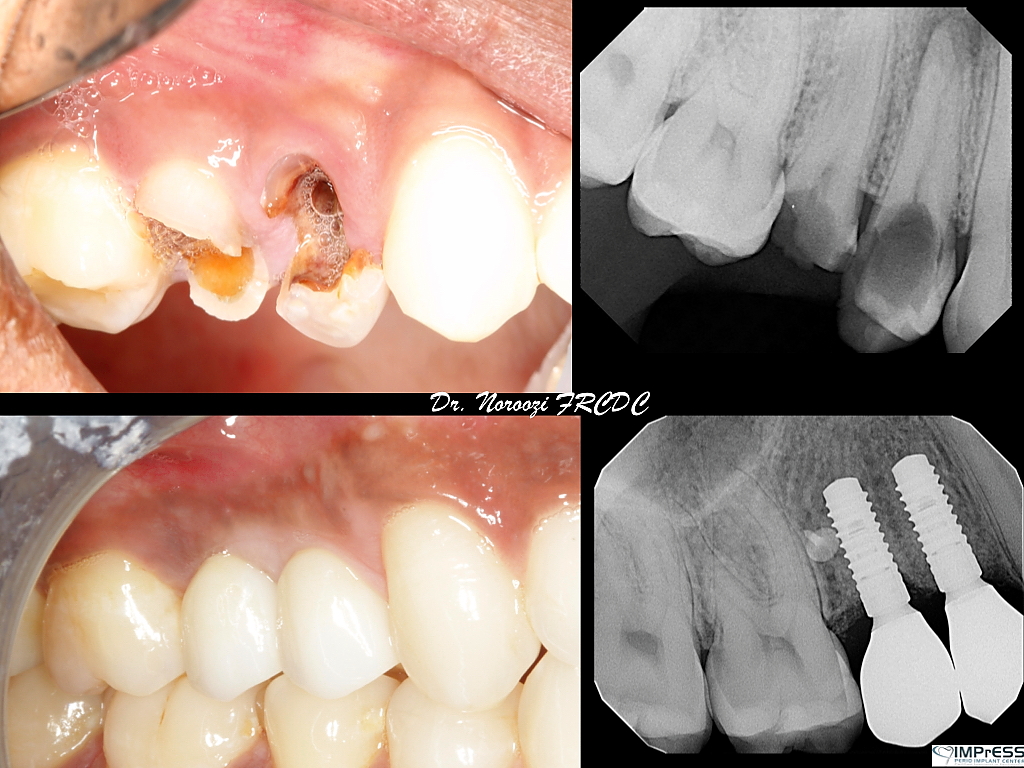

Before & Afters of Dental Implant Patients

Complete Dental Implant Cases Gallery

Surgical advances with SAME-DAY IMPLANTS in Vancouver BC

Using the most recent advances in dental implant technology, Dr. Noroozi is able to place single stage implants. These implants do not require a second procedure to uncover them but may require a minimum of six weeks of healing time before artificial teeth are placed. There are even situations where the implant can be placed at the same time as the tooth extraction and the artificial tooth can be inserted immediately following the implant placement – further minimizing your number of surgical procedures.

General Disclaimer: The results in the photographs are examples only and do not imply any certainty of the result of a procedure, and all outcomes are subject to the circumstances of the individual patient.